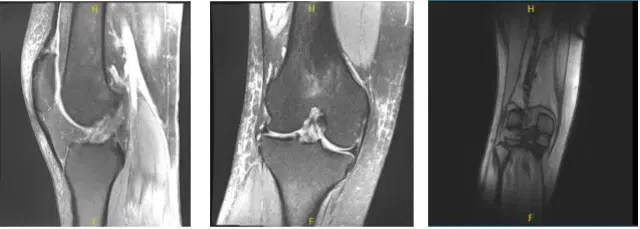

MRI-3T Right Knee non-contrast

Examination of the lateral tibiofemoral compartment showed fraying and tearing of the lateral meniscus and the posterior horn as well as vertical tear of the body of the lateral meniscus. Debridement of lateral meniscus was performed.

There was a free edge tear of the anterior horn of the lateral meniscus also, which was debrided. Decision was made to repair the lateral meniscus considering that it was reducing very well.

Flexible FAST-FIX sutures were used to pass horizontal mattresses x2. A good repair was achieved. Spinal needle was done to fenestrate the capsule of the lateral meniscus in the region of the repair. Microfracture chondroplasty of the intercondylar notch was performed from the holes.